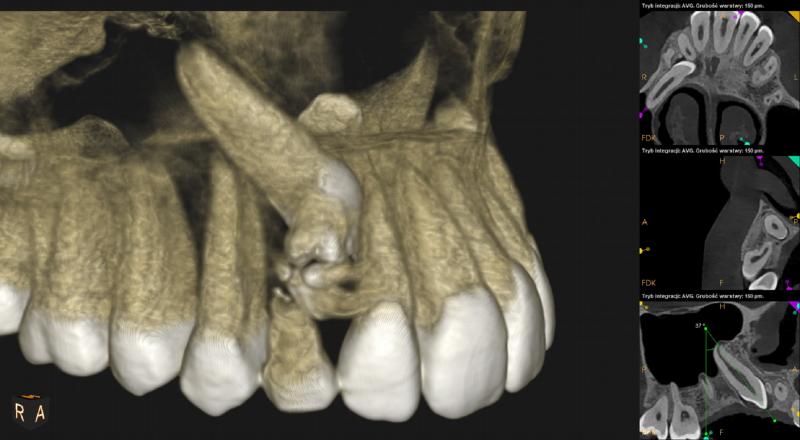

Nad zębem 53 owalny obszar otoczony rąbkiem przejaśnienia, wypełniony masą drobnych odontoidów (12,5mm x 10mm x 8,5mm). Obraz radiologiczny odpowiada zębiakowi zestawnemu (Odontoma compositum).

Ząb 13 – zatrzymany. Położony pionowo skośnie, koroną skierowany w stronę mezialną i podniebienną. Zrotowany w stronę mezialną.

Wierzchołek korzenia zęba zagięty, w świetle zatoki szczękowej. Widoczna resorpcja korzenia zęba 12.